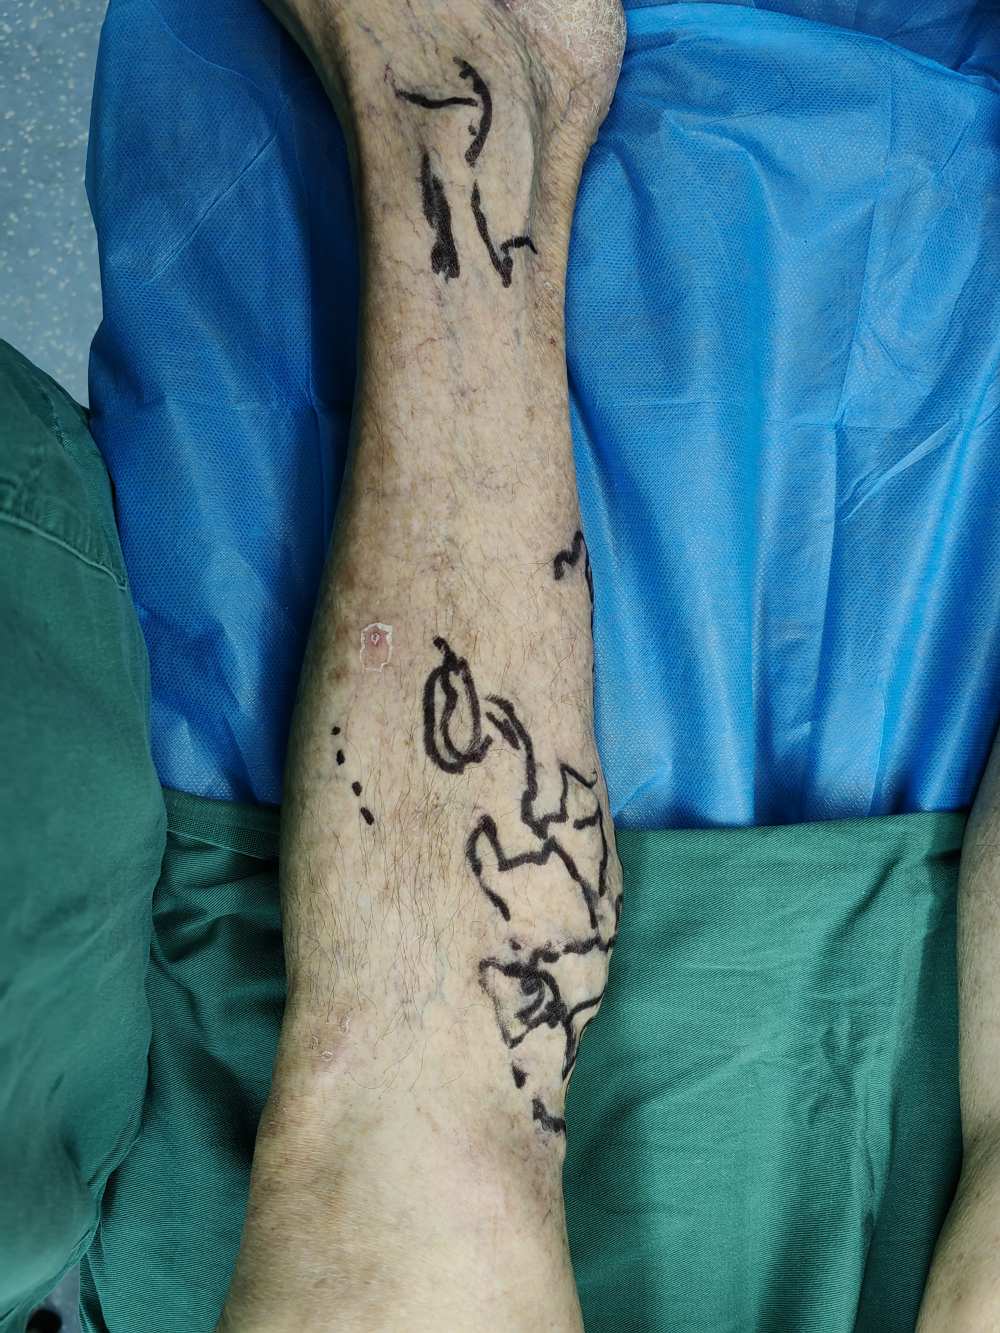

二、 下肢靜脈微創手術

下肢靜脈曲張(zhāng)為常見病及(jí)多發病,臨床表現主要為下肢血管迂曲(qǔ)、下肢腫脹(zhàng)、疼(téng)痛、局部皮膚(fū)色素(sù)沉著、嚴重時出現局部潰瘍、潰爛。對於有嚴重臨(lín)床表現者均需(xū)要手術治療。傳統手術為大隱靜脈高位結紮+主幹剝脫(tuō)+曲張靜(jìng)脈剝脫,相比微創手術其缺點(diǎn)是創傷大、恢複慢、下肢皮膚麻木感、不美觀等。我院(yuàn)外(wài)二科自2022年底始常規開展下肢靜脈微創手術,運用穿刺技術進行血管腔內消融閉合,硬化劑注射(shè)閉合曲張血管,從而達到傳統手術一樣效果,其優點為無切口、損(sǔn)傷小、恢複(fù)快、術後疼痛輕微(wēi)、無明顯(xiǎn)皮膚麻木感(gǎn)、美觀等。下肢靜(jìng)脈曲張主要危險因(yīn)素有:重(chóng)體力勞動、長(zhǎng)時間站(zhàn)立工作、體型粗(cū)大、妊娠(shēn)、長時(shí)間座位工作等。預防下肢靜脈曲(qǔ)張措施有(yǒu):改變工作方式,如(rú)需長時間站立或者座位工(gōng)作者,可以穿靜脈曲(qǔ)張彈力襪;保持良好生活習慣,堅持適當體育鍛煉(liàn)等。外二科現常規開展血管外科相關(guān)手術(shù),如下肢靜脈曲張微創(chuàng)手(shǒu)術、下肢靜脈血栓相關手(shǒu)術治療、血管瘤/血管(guǎn)畸形介(jiè)入治療、下肢動脈常規介入手術、內髒血管病變相關介入手術、內髒出血栓塞術(shù)等(děng)。

手術中

手術前(qián)及(jí)術後一個月